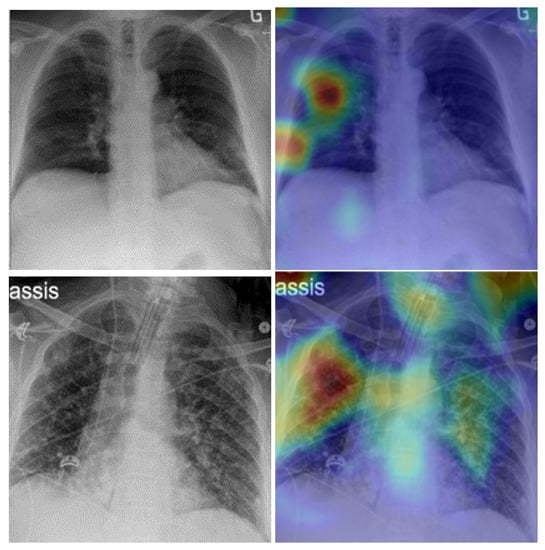

5. Model Explainability